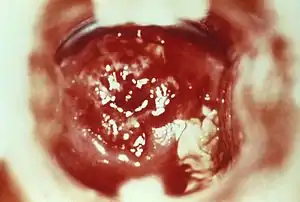

| HSV cervicitis | |